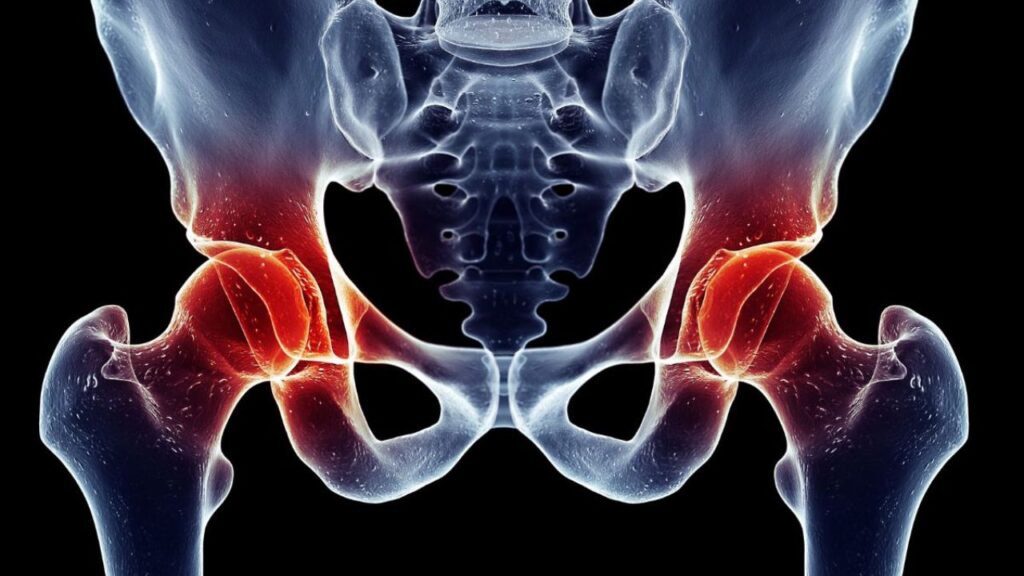

Diagnóstico preciso O diagnóstico é estabelecido através da avaliação clínica detalhada, onde o especialista analisa a marcha e a amplitude de movimento do quadril. Exames de imagem são fundamentais para confirmar a gravidade do desgaste. A radiografia simples costuma ser o primeiro passo para visualizar o estreitamento do espaço articular e as deformidades ósseas, enquanto a ressonância magnética pode ser solicitada para avaliar lesões associadas nos tecidos moles e o estado do osso subcondral.